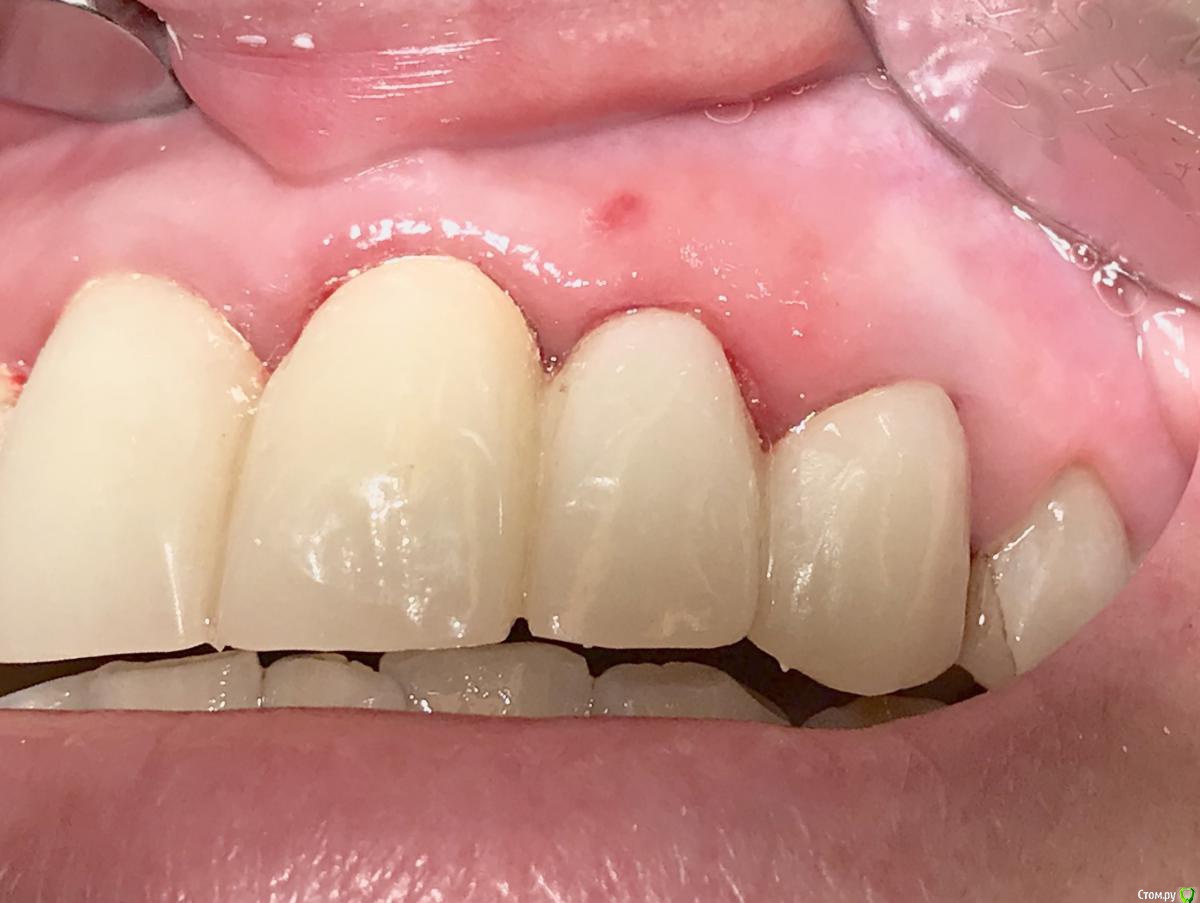

колесников Опубликовано 10 мая, 2019 Поделиться Опубликовано 10 мая, 2019 Удаление с консервацией под мост,закрыто быстрымноймаером. Вид через 3 недели . Удаление повязки,под ней не созревший гранулят,замена на овоид. Следующий визит через месяц,посмотрим будет ли стабилен десневой контур. 3 Ссылка на комментарий